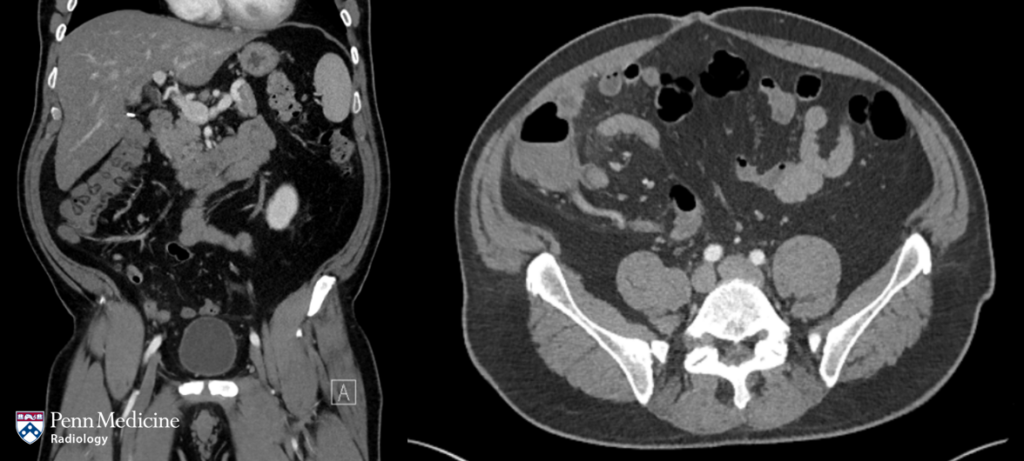

70-year-old woman with fever and left flank pain

A 70-year-old woman presented with fever and left flank pain. The patient's history was significant for chronic heart failure, chronic v…